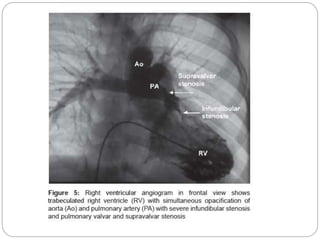

 RV angiogram (anteroposterior [AP] cranial, left

anterior oblique [LAO] view) shows simultaneous

opacification of aorta and PA, RVOT obstruction

and PA anatomy